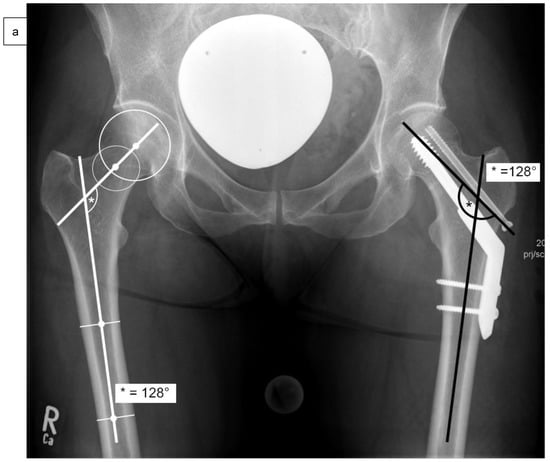

As well as epidemiological patient parameters and the Kellgren–Lawrence score at the time of hospital admission, the femoral neck angles (°) were captured in comparison to the opposite side (Figure 2a) after reduction and surgical stabilization six weeks postoperatively by using biplanar conventional radiographs. Valgus reduction was defined as a femoral neck angle of more than 5° in comparison to the opposite side. Then, the cohort group was divided into group “A”, which included patients with anatomical reduction, and group “B”, which consisted of patients with valgus reduction of the Garden type III femoral neck fracture. Further on, the angle of the 2- or 4-hole SHS plate (°), the tip-apex distance (mm) as described by Baumgaertner et al. (Figure 2b), and the angle between SHS and ARS (°) were measured in frontal (Figure 2c) and axial planes (Figure 2d) of the intraoperative or postoperative X-rays [].

Figure 2.

Measurement of the femoral neck angle (*) compared to the contralateral side (°), defined as the angle between the femoral neck axis and the bisecting line of the femoral shaft (a). The tip-apex distance (TAD) was defined as the calibrated summation of the distance between the tip of the SHS and the apex of the femoral head on anteroposterior and (not demonstrated) lateral radiographs (mm) (b), and the angle between SHS and ASR in the frontal plane (#) (c) and the axial plane (x) (d) by using biplanar conventional radiographs, six weeks postoperatively.